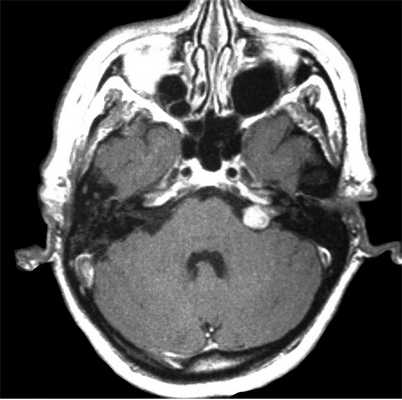

Более точно установить диагноз «невринома слухового нерва» помогает рентгенография и методы нейровизуализации. На ранних стадиях при малых размерах невриномы (до 1 см) она, как правило, не визуализируется при помощи КТ головного мозга. Поэтому проводят рентгенографию черепа с прицельным снимком височной кости. В подтверждение диагноза вестибулярной шванномы свидетельствует расширение внутреннего слухового прохода. Поскольку невриномы хорошо поглощают контраст, возможно использование КТ с контрастированием. При этом визуализируется образование с четкими гладкими контурами.

МРТ головного мозга в случае невриномы выявляет на Т1-взвешенных снимках гипо- или изоинтенсивное, а на Т2-взвешенных - гиперинтенсивное образование. Для опухолей размером 3 и более см характерна гетерогенность сигнала, связанная с наличием в них кистозных участков. Возможна визуализация деформации ствола мозга и мозжечка. При проведении контрастной МР-томографии в 70% наблюдается гетерогенное накопление контраста.

Оптимальными способами визуальной диагностики являются компьютерная томография (КТ) и магнитно-резонансная томография (МРТ) головного мозга. Эти исследования принято проводить с контрастным усилением, так как оно позволяет обнаружить даже небольшие новообразования [14] . Иногда опухоль обнаруживается случайно — при проведении КТ или МРТ головного мозга по другому поводу [13] . По результатам этих исследований можно поставить точный диагноз, выявить локализацию опухоли, её размеры, структуру, отношение к окружающим тканям задней черепной ямки, спланировать тактику хирургического или радиологического лечения [12] .

- Церебральную нейровизуализацию. Применяется при новообразованиях черепных нервов. Контрастная КТ головного мозга способна выявить невриномы размером более 1 см. Церебральная МРТ обладает большей информативностью, лучше визуализирует состояние окружающих опухоль тканей.

На Т2-взвешенных МРТ головного мозга невриномы имеют округлую или овальную форму, изоинтенсивны или слегка гиперинтенсивнее белого вещества, хорошо видны на фоне яркого ликвора цистерны. Крупные опухоли могут подвергаться кистозной дегенерации и включать сосуды. Мелкие невриномы имеют компонент во внутреннем слуховом проходе и как бы “утолщают“ нерв на МРТ изображениях. Как показывает опыт МРТ СПб полностью внутриканальцевые невриномы встречаются редко. МРТ в СПб при шванномах мы проводим обычно с контрастированием. Контрастирование неврином при МРТ с контрастированием хорошее, обычно однородное. Нельзя забывать, что во внутреннем слуховом проходе также может быть воспалительный процесс (неврит), приводящий к сходной клинической симптоматике. При МРТ неврит виден как отёк нерва, имеется контрастное усиление на МР томограммах.

МРТ головного мозга. Невринома слухового нерва слева с внутриканальцевым компонентом. Аксиальные Т1-зависимая МРТ, Т1-зависимая МРТ с контрастированием, и корональная Т1-зависимая МРТ с контрастированием.